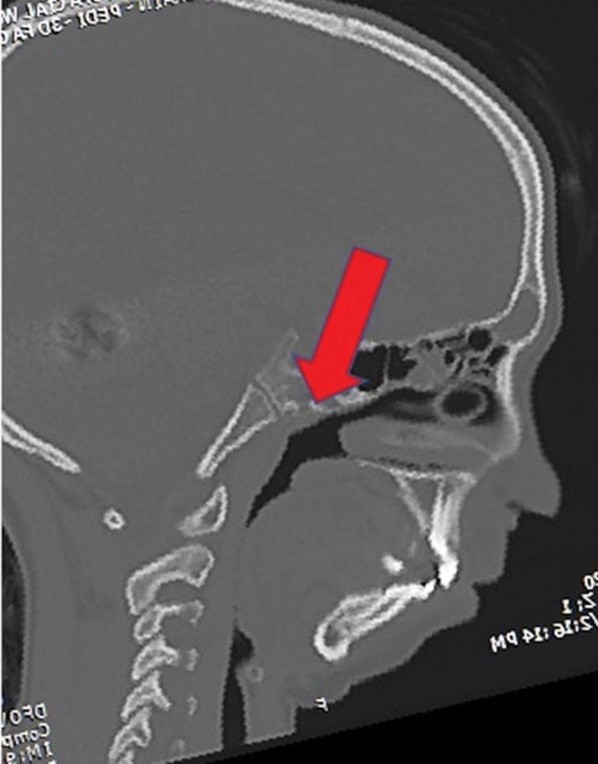

Airway obstruction

2D CT scan showing blocked airway

Radiographical features source 7